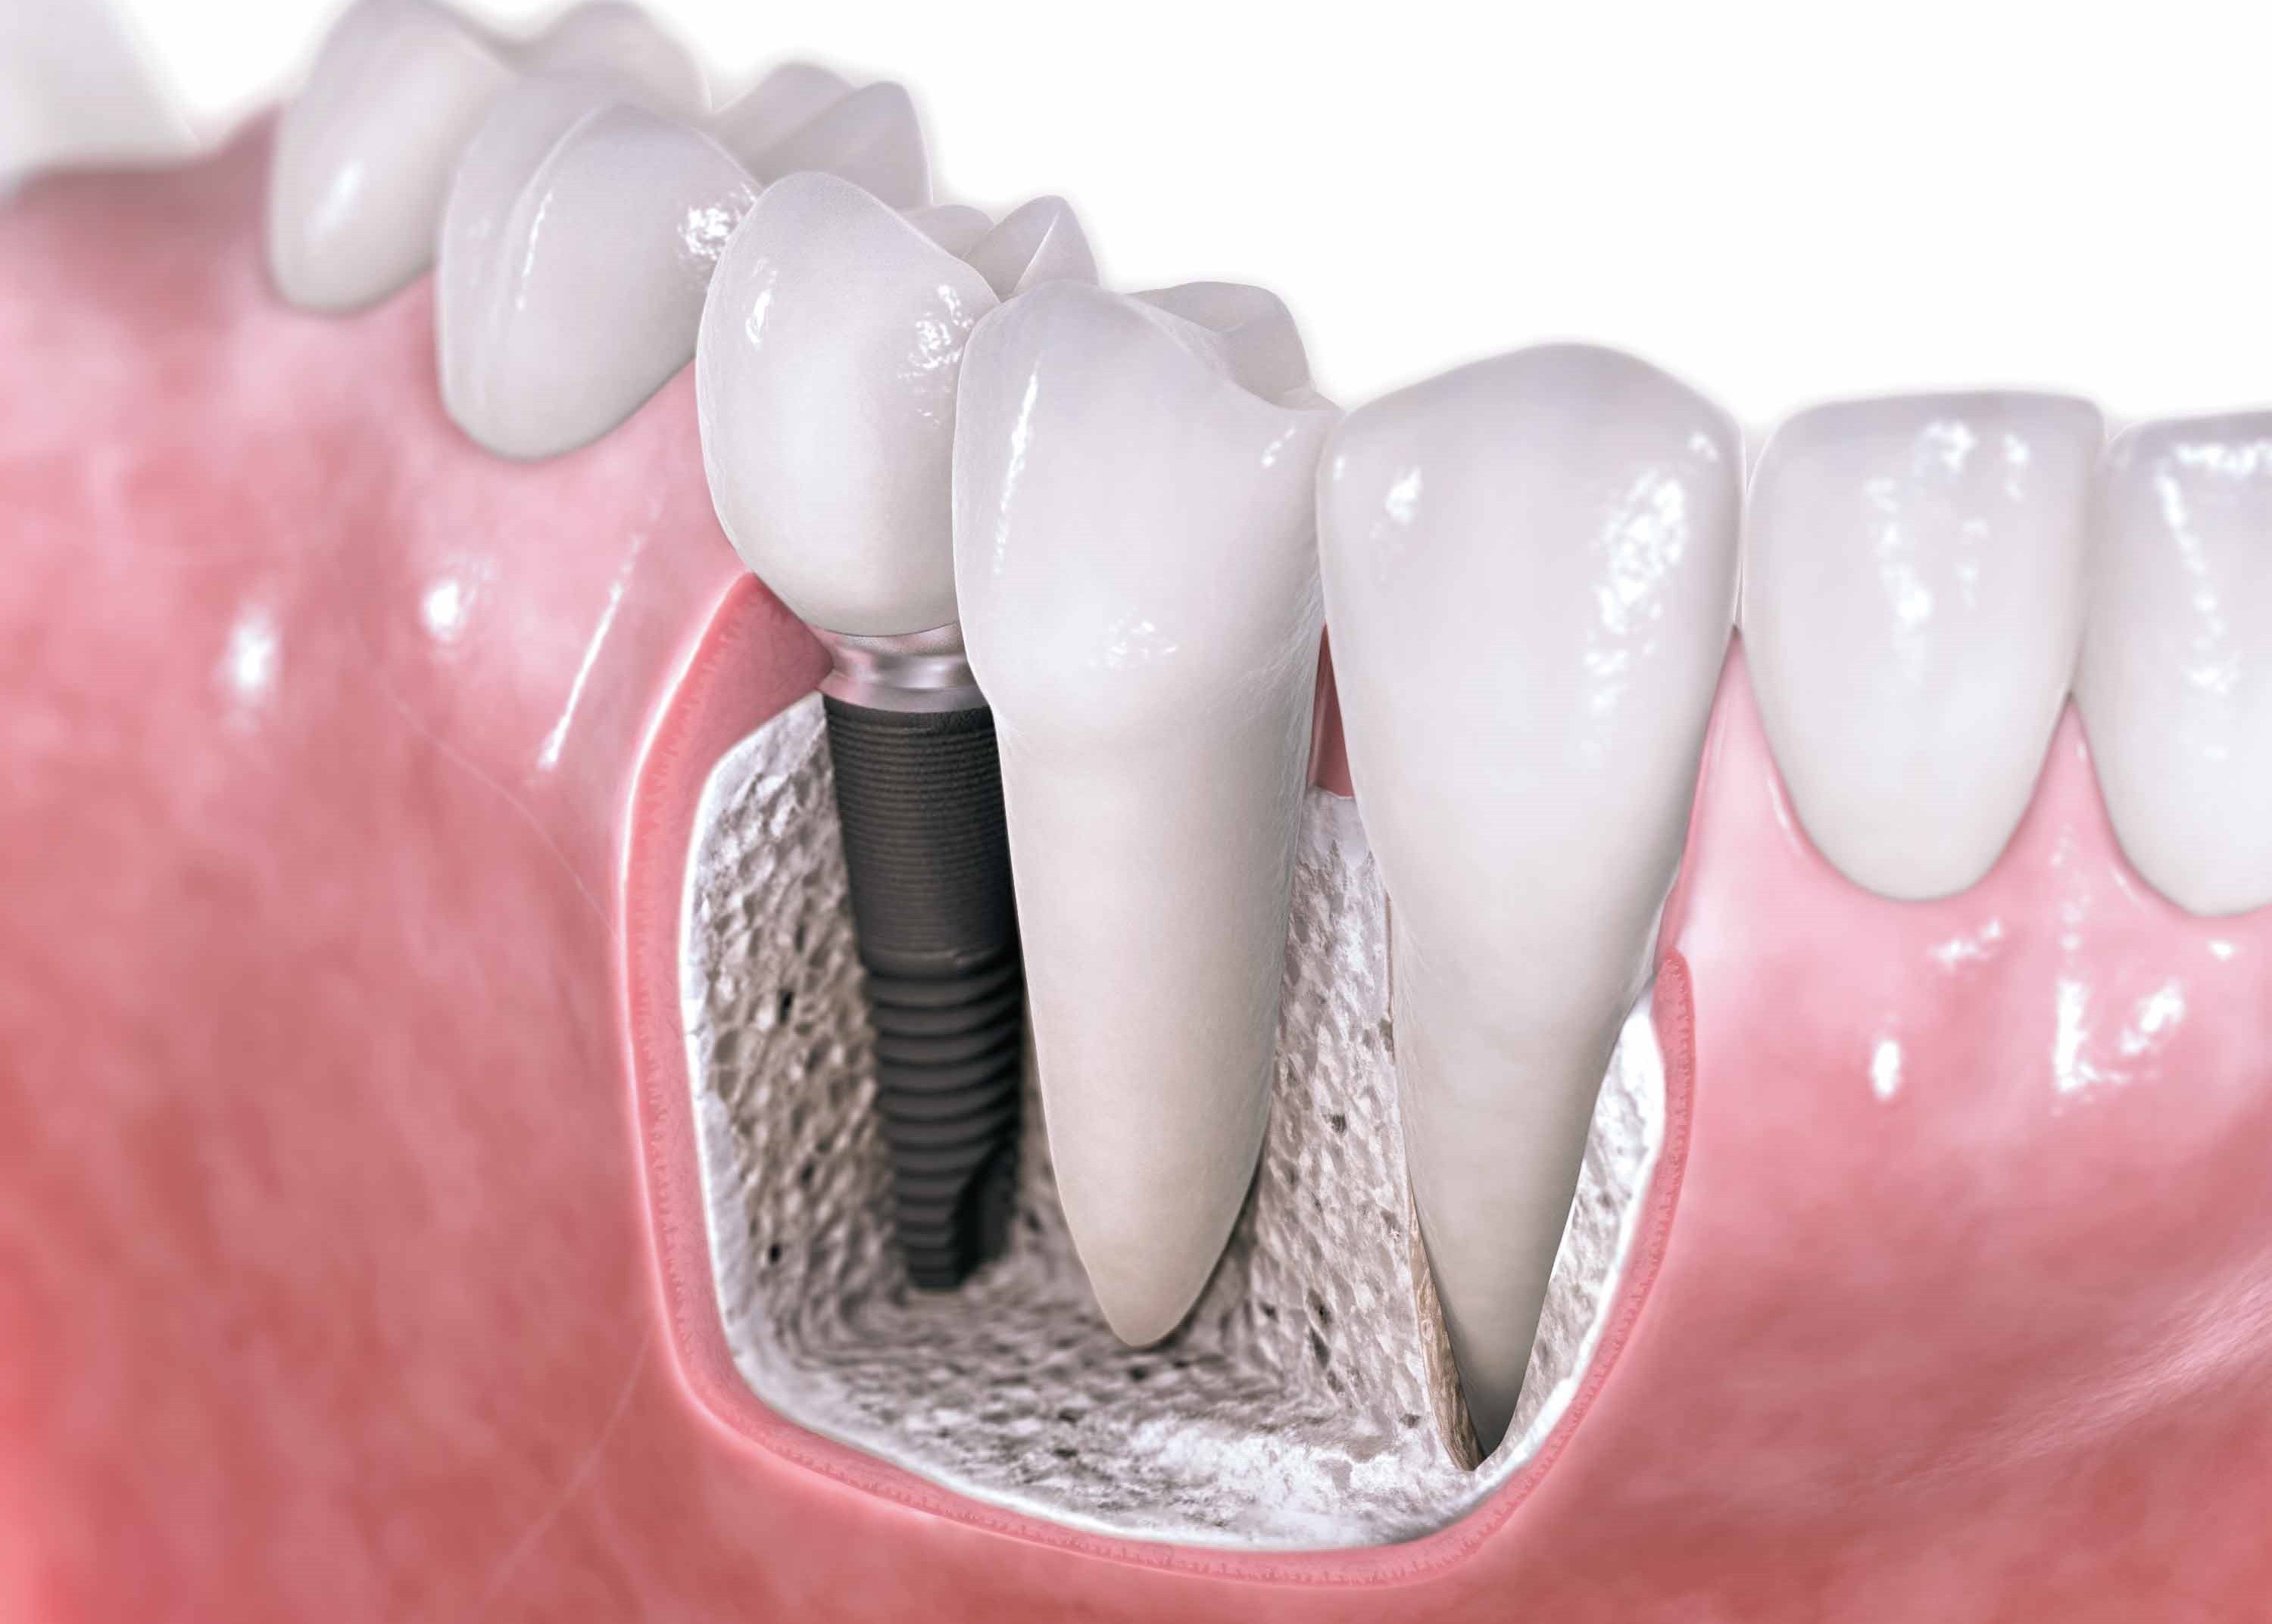

Son estructuras de titanio de formas similares a las raíces de los dientes naturales, que son colocadas en los huesos de los maxilares. Una vez que los implantes se han integrado al organismo mediante un proceso natural por el cuál el titanio y el hueso se unen, y es llamado “óseointegración”. Posteriormente a estas estructuras se les atornilla la parte del diente o dientes que se substituyen, remplazando naturalmente al diente en función y estética. Este procedimiento en el mayor de los casos es realizado SIN dolor.

Los implantes dentales han hecho posible dar naturalidad, función, estabilidad protésica, sonrisas confiables y naturales con un alto grado de éxito.

Los Implantes Dentales son la más avanzada técnica disponible para reponer los dientes faltantes. Además de verse y sentirse como dientes naturales le permiten al paciente: